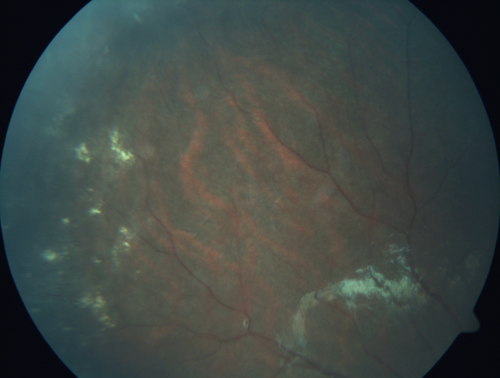

Familial Exudative Vitreoretinopathy - FEVR - Stage 4b OD

10 year old child with poor vision OD from birth.  The left eye had vascular remodelling in the temporal periphery with preretinal abnormalitlies seen on OCT.  The patient never returned for a fluorescein angiogram.  Left eye is either stage 1 or stage 2. no family history